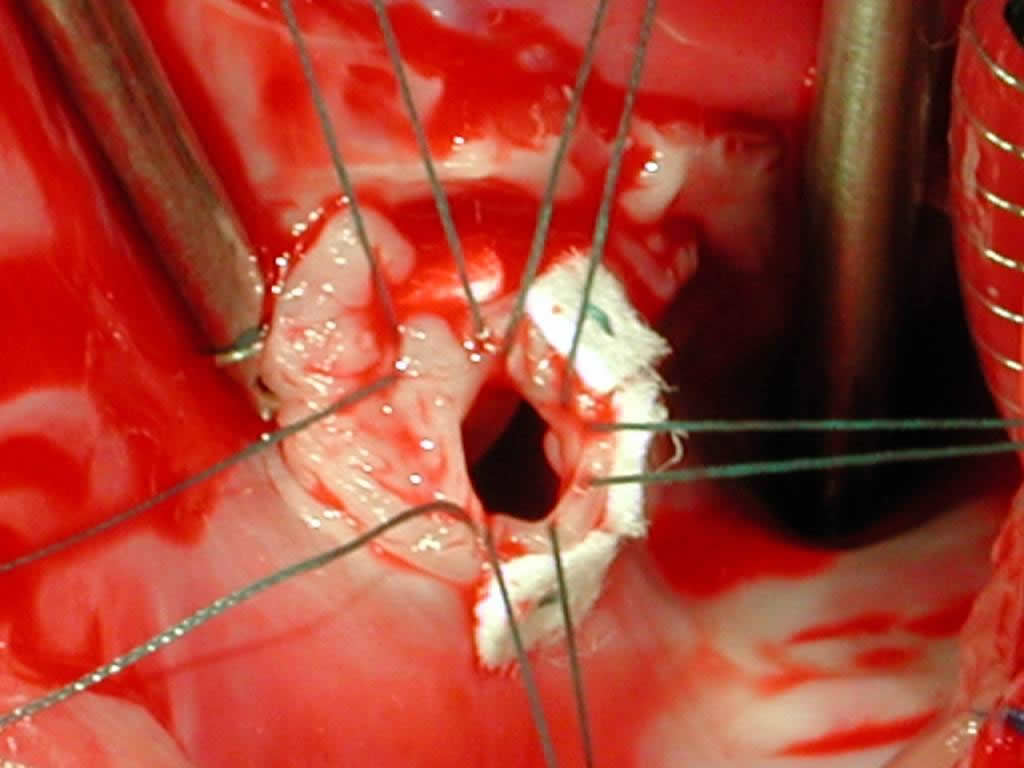

Figure 11 shows the placement of 5 pledget-supported Ticron sutures around the circumference of the ventriculo-atrial defect.

Figure 12 shows a 0.4-mm thickness Gore-Tex® cardiovascular patch in which sutures have been placed, lowered into the field.